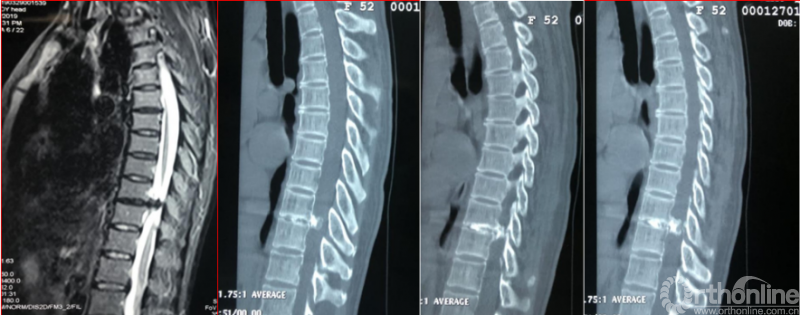

术前诊断及评分

JOA评分:3分

ASIA等级:C级

诊断:

1:多节段胸椎黄韧带骨化症双下肢不全瘫

2:腰椎内固定术后

3:Ⅱ型糖尿病

术前资料